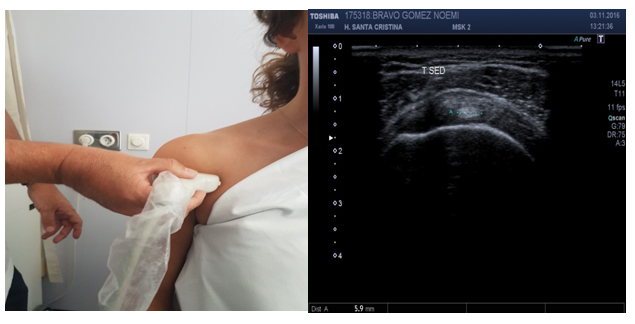

US is the most difficult technique to perform by radiologists. US is operator dependent. The learning curve is time consuming. Specific operative knowledge on Knobology (knowledge of US equipment), sonoanatomy, patient’s and probe’s position are required.8 On evaluation of images, radiographies and magnetic resonance imaging have an anatomical representation. On the contrary, US images are harder to understand.8 The position of the patient may favor the exposition of anatomical structures, especially on shoulder evaluation (Figure 1). When evaluating an anatomical structure, the probe on long axis position (longitudinal evaluation) is quite different than the probe on short axis position (transversal evaluation).

Figure 1 (A) The position of the shoulder may favor the exposition of anatomical structures. Supraspinatus tendon is better exposed on the “Marilyn Monroe pose”, (B) while supraspinatus tendon is better exposed on the “military position”.